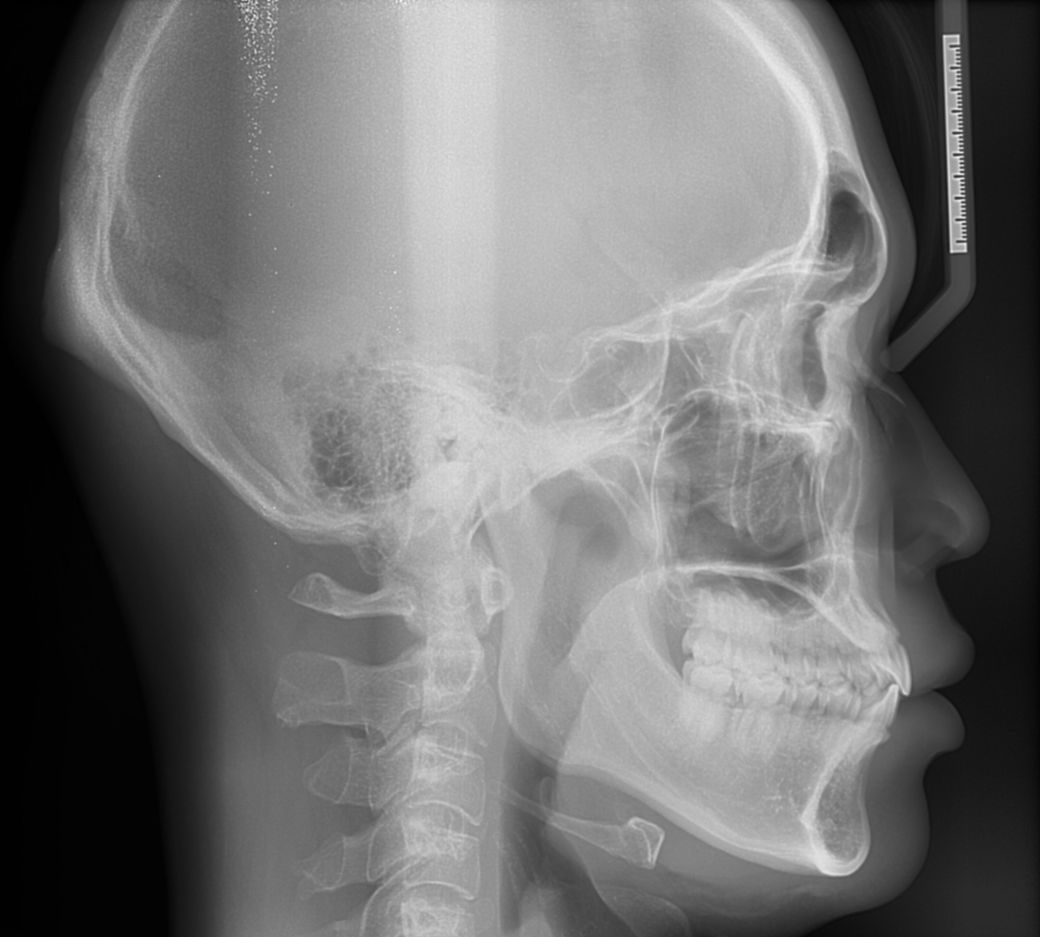

구강악외과에서 턱정밀상담 결과 하관평균길이가 성인남성평균보다 길고 돌출되었다고 들은 이후에 신경이 쓰여 수술 질문좀 하고싶습니다

실제와 사진은 다르겠지만 ct와사진만보고 개인적은 의견 적어주시면 참고하도록 하겠습니다

현재는 수술이 필요할 정도로 하악이 돌출되거나 발달하지는 않았습니다.

지극히 일반적인 턱으로 억지로 턱을 넣을 경우에 이에 따른 부작용도 생각해야 하며

수술로 인해 오히려 소하악증이나 코골이 등의 문제가 생길 수 있어 자연 그대로가

가장 안전할 수 있습니다. 감사합니다.